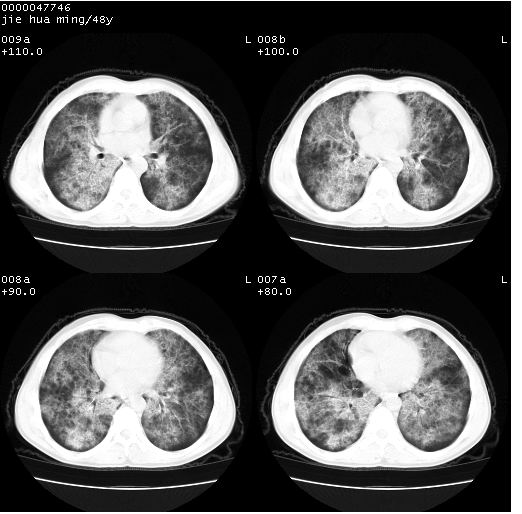

以下是引用dr.yang在2008-5-1 6:25:00的发言:[br]两肺广泛毛玻璃样的片状影,密度不均,边缘欠清,呈碎石路样改变,[br]考虑,1双肺间质性肺炎,2肺泡蛋白沉积症3支气管肺泡癌[br]

以下是引用hhcckk在2008-5-1 8:06:00的发言:[br]支持肺泡蛋白沉积症[br]依据:[br]1、病灶边缘清楚----地图征[br]2、病灶内部小叶间隔或小叶内间隔增厚所形成的网格状影----碎石路样表现[br]3、抗炎治疗无效(炎症抗炎治疗有效)[br]4、纵隔内未见肿大淋巴结(肺泡细胞癌时常有)[br][br]附肺泡蛋白沉积症资料[br][br]肺泡蛋白沉积症(pulmonary alveolar proteinosis)是一种原因不明的以肺泡腔内大量含脂糖蛋白样物质沉积为特征的疾病。[br]病理改变:(1)肺泡和细支气管腔内充满大量含脂糖蛋白样的粘稠物质,该物质为颗粒状或絮状的糖原pas染色阳性的磷脂蛋白。(2)肺泡壁及其间隔无异常改变。胸膜和淋巴结不受累及。(3)晚期可出现弥漫性肺间质纤维化。[br]临床表现:(1)好发年龄30~50岁,男性多于女性,偶见于儿童;(2)主要症状为呼吸困难、咳嗽、低热、消瘦、低氧血症和杵状指等。1/3的患者无症状。(3)实验室检查:痰液或肺泡灌洗液中可找到pas染色阳性颗粒物质。[br]hrct表现:肺泡蛋白沉积症具有特征性改变,即“碎石路样”表现(crazy-paving appearance,cpa)。主要包括(1)斑片状磨玻璃影:指肺野密度朦胧增加,内可见肺血管纹理影,系肺泡腔内充满低密度的磷脂蛋白物质所致。(2)其内部小叶间隔或小叶内间隔增厚所形成的网格状影,为小叶间隔水肿、肺泡壁内淋巴细胞和巨噬细胞浸润以及小叶内淋巴管扩张的缘故。(3)病灶边缘清楚,呈地图样分布于肺野外围或肺门及中央区。[br]

以下是引用zsl6918在2008-5-1 7:35:00的发言:[br]双肺磨玻璃样病变,可见铺碎路石征,病变区与正常区交错。边界清晰。符合肺泡蛋白质沉着征,高分辨扫描会更清楚漂亮。建议临床肺泡灌洗。

以下是引用yangyudong333在2008-5-1 5:36:00的发言:[br][br] 两肺广泛毛玻璃样的片状影,密度不均,边缘欠清,呈碎石路样改变,[br]考虑,1双肺间质性肺炎,2肺泡蛋白沉积症[br]